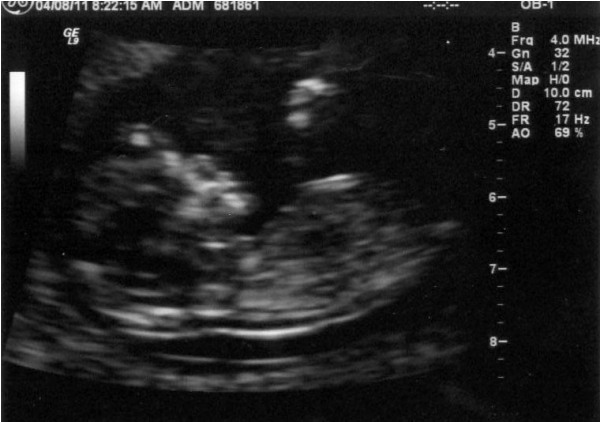

We had yet another ultrasound today. The baby's weight is estimated at 2 pounds 3 ounces which puts him in the 50th percentile for his gestational age -- right at average in other words. The sonographer made a comment about how she had to chase the baby around to get the measurements she wanted. It made me think... if she has to chase him around now, when he's in a very enclosed space, what does that imply about how much we'll have to chase him when he learns to crawl and walk?

Here is the picture of his face that we got today. Not quite as clear as the one two weeks ago but still very recognizable. It looks like he's laughing to me with the way he has his mouth open.

Here is a hand with the fingers extended. We don't have a picture of it, but we also saw his other hand, which was clenched into a fist with his arm bent. It looked like he was getting ready to give me a good punch!

Here is a foot.